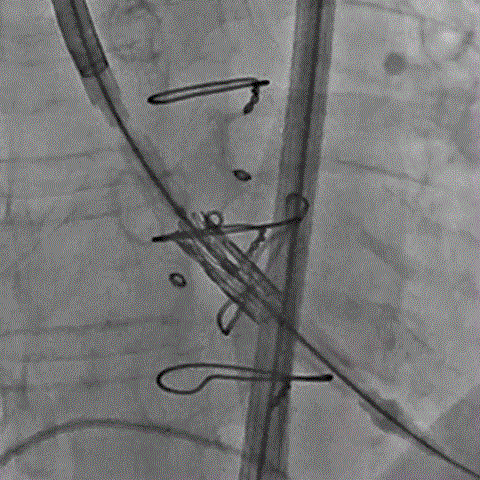

术前经详尽影像学重建和评估,该款人工生物瓣显影不理想,通过CT重建测量瓣环直径,评估冠脉梗阻风险。考虑到患者横位心,主动脉迂曲严重,最终选用经心尖入路,植入21# Renato球扩式瓣中瓣。手术顺利,瓣中瓣植入位置理想,功能表现出色,主动脉瓣峰值流速由术前3.4m/s下降至2.0m/s,平均跨瓣压差由术前32mmHg下降至8mmHg。经食道超声观察无瓣周漏及瓣中反流。

术前经详尽影像学重建和评估,CT重建测量瓣环直径,评估冠脉梗阻风险及外周血管条件。最终采用经股动脉入路植入21# Renato球扩式瓣中瓣。手术顺利,瓣中瓣植入位置理想,功能表现出色,主动脉瓣峰值流速由术前4m/s下降至2m/s,平均跨瓣压差由术前40mmHg下降至6mmHg。经食道超声观察无瓣周漏及瓣中反流。